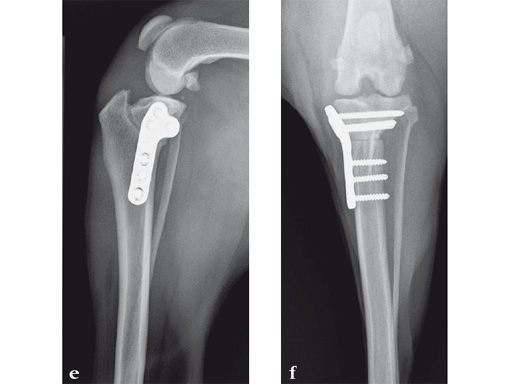

A 10-year-old female, spayed, 6.0 kg cat had a partial tear of the left cranial cruciate ligament, meniscal mineralization, and a medial meniscal tear. The cat was treated with a partial meniscectomy and TPLO . A 2.0 mm TPLO plate was perfect for this cat due to the slope of the tibial plateau (25) and the size of the cat. Three 2.0 mm locking screws were used proximally and three 2.0 mm cortex screws were used distally. The contour of this plate does not perfectly match the contour of the proximal tibia, but use of locking screws in this segment avoids any potential angulation of the segments as the screws are tightened. The cat healed uneventfully and returned to normal function.